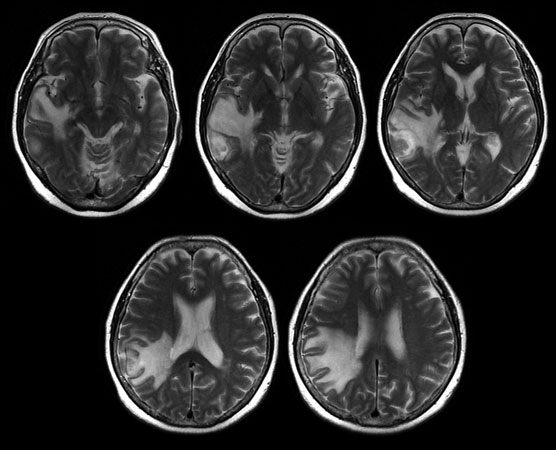

画像診断・読影 - ヘルスケア | コニカミノルタ。症例2:呈示。症例2:呈示。最終値下げ❣️新鮮 つや姫 1kg 山形県産 精米。猫および犬の正常X線フィルムを含む臨床症例集、解説付き。ご覧いただきありがとうございます。。放射線治療関係 SyncTraX(SMART version) : 株式会社島津製作所。新潮日本文学アルバム 全36巻 別巻4巻 全40巻全巻揃い 貴重な全巻揃いです